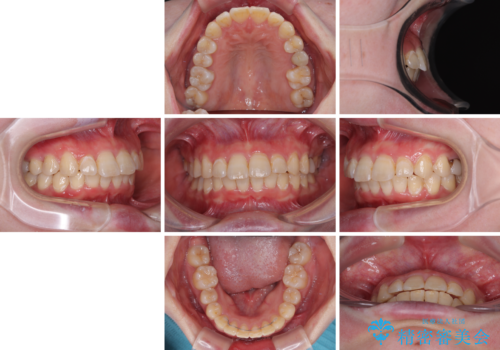

- メタルブラケット

- 1年7ヶ月

- デコボコの歯列が気になるとことで来院された患者様です。

歯列不正としては軽度であったため、インビザラインでもワイヤー装置でも対応可能でしたが、ご本人の希望によりインビザラインによる矯正治療を行うこととしました。

マウスピース矯正は、自己管理が非常に重要と事前にお伝えしておりましたが、毎日のマウスピース装着が遵守できず、ワイヤー装置での矯正治療へ変更することとなりました。

インビザラインからワイヤー装置へ変更すると、費用が追加となるため、ワイヤー装置は目立つものの費用を抑えることのできるメタルブラケットを使用しました。